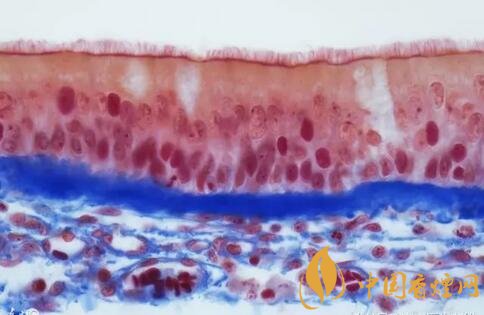

在經(jīng)過長(zhǎng)期戒煙之后呢,人體肺部的纖毛還會(huì)重新的生長(zhǎng)。肺部的纖毛起到過濾雜質(zhì)和預(yù)防感染的重要作用,能增強(qiáng)戒煙者的免疫力和抗病能力。抽煙者的支氣管功能也隨之上升,能夠正常的呼吸,呼吸能力逐漸增強(qiáng)。

吸煙對(duì)肺的最大影響是導(dǎo)致肺部纖毛損壞,經(jīng)常抽煙的話,肺部纖毛將會(huì)逐漸失去作用并且難以再生。纖毛還能夠幫助肺清除黏液,吸煙者經(jīng)??人缘脑蛞彩且?yàn)檫@些纖毛損壞造成的。

一般在戒煙三個(gè)月之后呢,人體的肺部纖毛會(huì)恢復(fù)到一個(gè)正常的值,可以去清除死亡或者受損的細(xì)胞,在這個(gè)時(shí)期支氣管也將恢復(fù)健康。這個(gè)時(shí)候抽煙者的肺部會(huì)慢慢地恢復(fù)到健康人的樣子,至于時(shí)間的長(zhǎng)短要因人而異。一般來說,煙齡越長(zhǎng),肺部恢復(fù)健康所需要的時(shí)間也越長(zhǎng),所以對(duì)于長(zhǎng)期吸煙的人來說,一定要持之以恒,不能因?yàn)槎唐趦?nèi)看不到成效而放棄。